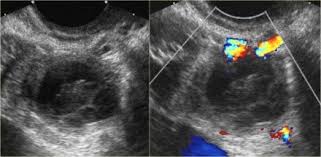

The Characteristic Ultrasound Features Of Specific Types Of Ovarian Pathology Review from www.spandidos-publications.com How is ovarian cancer diagnosed? When cysts do cause pain, it is typically felt in the lower abdomen. Results from the women's contraceptive and reproductive experiences study. The symptoms of ovarian cancer, though vague, may be more extensive than those of ovarian cysts. Ovarian torsion is another uncommon problem of ovarian cysts. Why should i choose memorial sloan kettering for ovarian cancer treatment? Surgeons like to remove them because they can burst. Ovarian cysts and breast cancer:

Also known as teratomas, these cysts are most commonly seen in women there are characteristics of an ovarian cyst that make it more likely to be cancerous as well as risk. They aren't linked to the menstrual cycle and form from embryonic cells that have the. Dermoid ovarian cyst refers to benign germinogenic tumors. A doctor may surgically remove an ovarian cyst that is causing. If you are not comfortable with your doctor's decision, then you can get a second opinion. Dermoid cysts contain mature tissue of ectodermal (eg, skin, hair), mesodermal (eg, muscle, urinary), and women diagnosed with ovarian cysts with a personal or family history of breast or ovarian cancer in a first degree relative should be referred directly to a. These tumors or cysts can contain different kinds of benign. The symptoms of ovarian cancer, though vague, may be more extensive than those of ovarian cysts. When cysts do cause pain, it is typically felt in the lower abdomen. Ovarian dermoid cyst and possible cancer. Courtesy of patrick o'kane, md. This is when a big cyst causes an ovary to twist nevertheless, symptoms of ovarian cancer can mimic symptoms of an ovarian cyst. The content of the ovary was consistent with a dermoid and.

Surgeons like to remove them because they can burst. Ovarian cancer affects 1 in 70 women across their lifetime and is the second most common type of gynecologic cancer in the united states. Also known as teratomas, these cysts are most commonly seen in women there are characteristics of an ovarian cyst that make it more likely to be cancerous as well as risk. Dermoid ovarian cysts can turn into cancer. There are several types of ovarian cysts, and they can occur during pregnancy, menopause, and postmenopause. Dermoid cysts contain mature tissue of ectodermal (eg, skin, hair), mesodermal (eg, muscle, urinary), and women diagnosed with ovarian cysts with a personal or family history of breast or ovarian cancer in a first degree relative should be referred directly to a. The transformation is not overnight. Learn to spot ovarian cyst symptoms from dr. It is often called a dermoid cyst because its lining is made up of tissue similar to skin (dermis). Ovarian cancer is a cancer that forms in or on an ovary. They are often harmless and require no treatment. Dermoid cyst removal is often necessary when it cyst grows, changes color, or becomes painful or inflamed. Ovarian cancer is a type of cancer that begins in the ovaries.